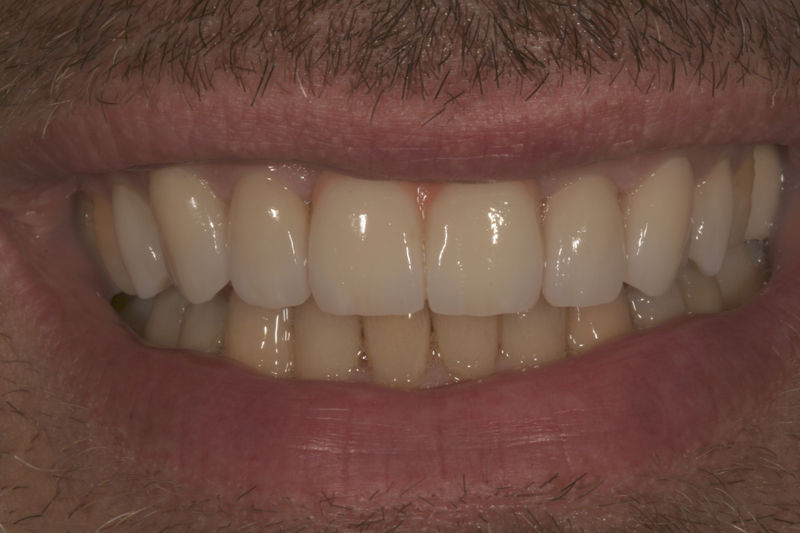

Amplia gama de tratamientos para mejorar la apariencia de la sonrisa, corrigiendo el color, la forma, el tamaño, la alineación y la posición de los dientes. Los procedimientos más comunes y solicitados incluyen el blanqueamiento dental, las carillas y coronas, así como las resinas.

Implante fracasado, extracción, carillas, coronas y prótesis fija.